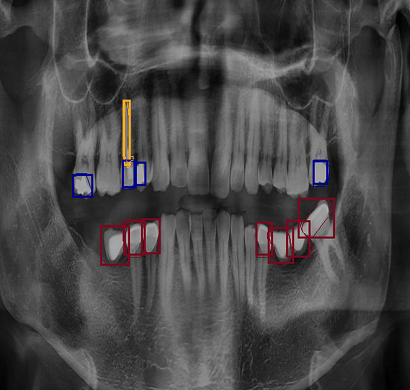

Orthopantomogram, commonly known as OPG, is a specialized panoramic dental X-ray that provides a comprehensive view of the entire mouth in a single image. It captures detailed visuals of the upper and lower jaws, teeth, jaw joints, sinuses, and surrounding bone structures, making it an essential diagnostic tool in modern dental and maxillofacial care. Unlike traditional intraoral X-rays that focus on a small area, OPG offers a wide-angle image that helps dentists and specialists evaluate overall dental health efficiently. It is widely used for detecting impacted teeth, wisdom teeth positioning, cavities, bone loss, jaw fractures, infections, cysts, tumors, and other abnormalities affecting oral and facial structures.

The OPG scan is quick, painless, and non-invasive. During the procedure, the patient stands or sits still while the machine rotates around the head, capturing a full panoramic image within seconds. The radiation exposure is minimal, making it a safe option for routine dental assessments and treatment planning. OPG plays a crucial role in various dental procedures, including orthodontic planning (braces), dental implants, root canal treatments, and oral surgeries.